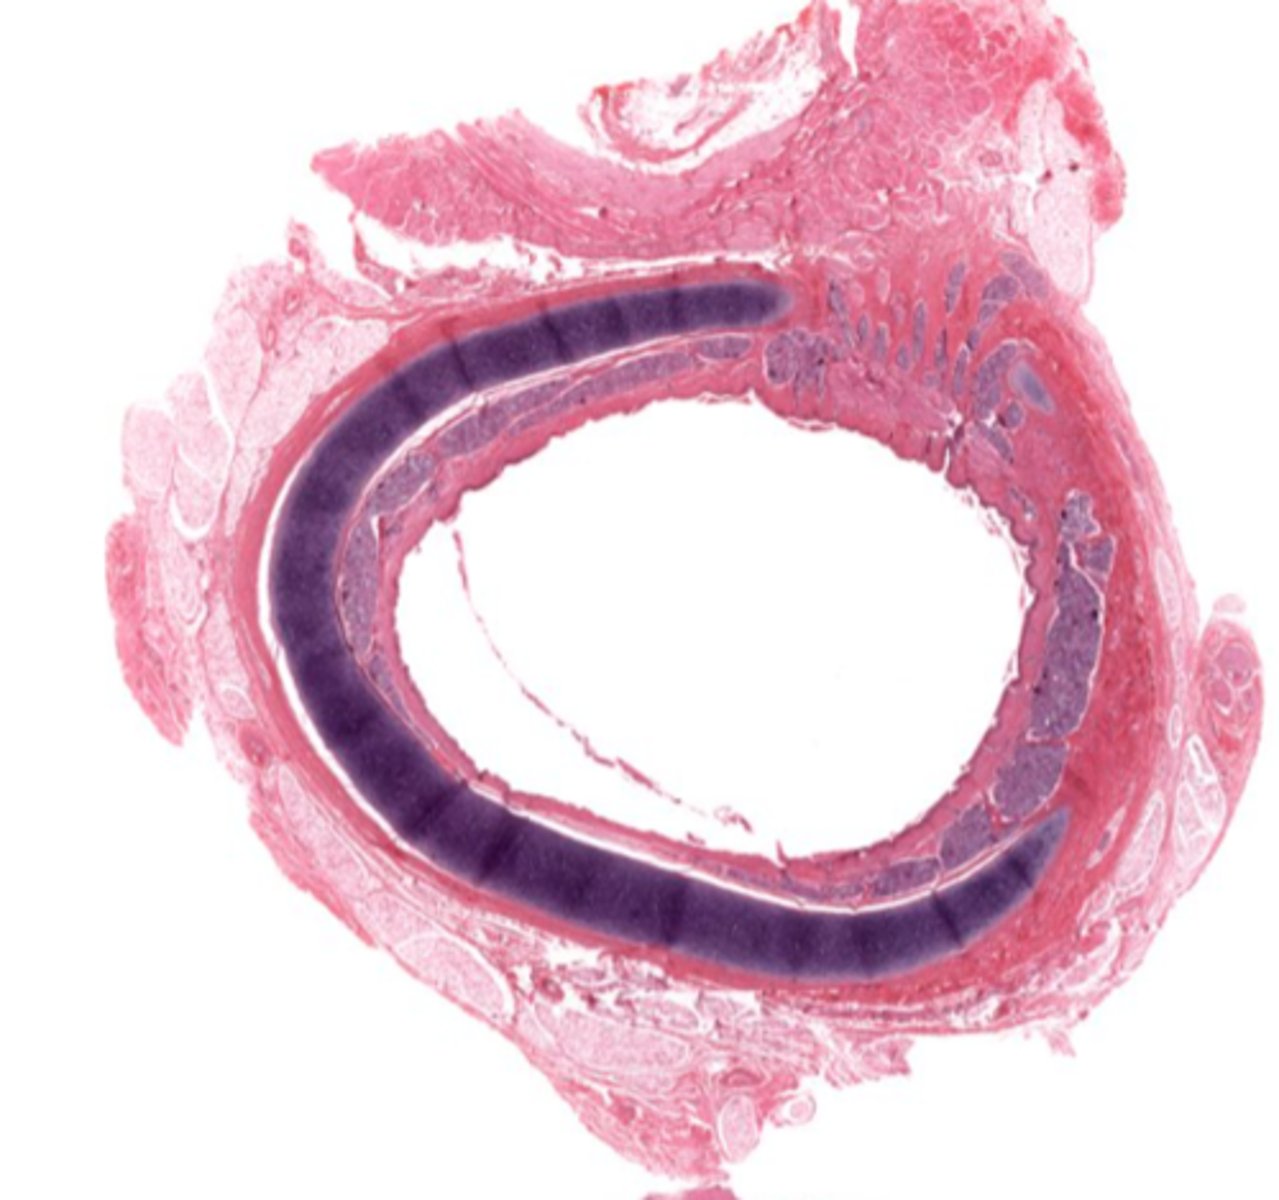

Identify the organ in cross section

trachea

Classify the epithelium of the trachea

pseudostratified columnar ciliated with goblet cells